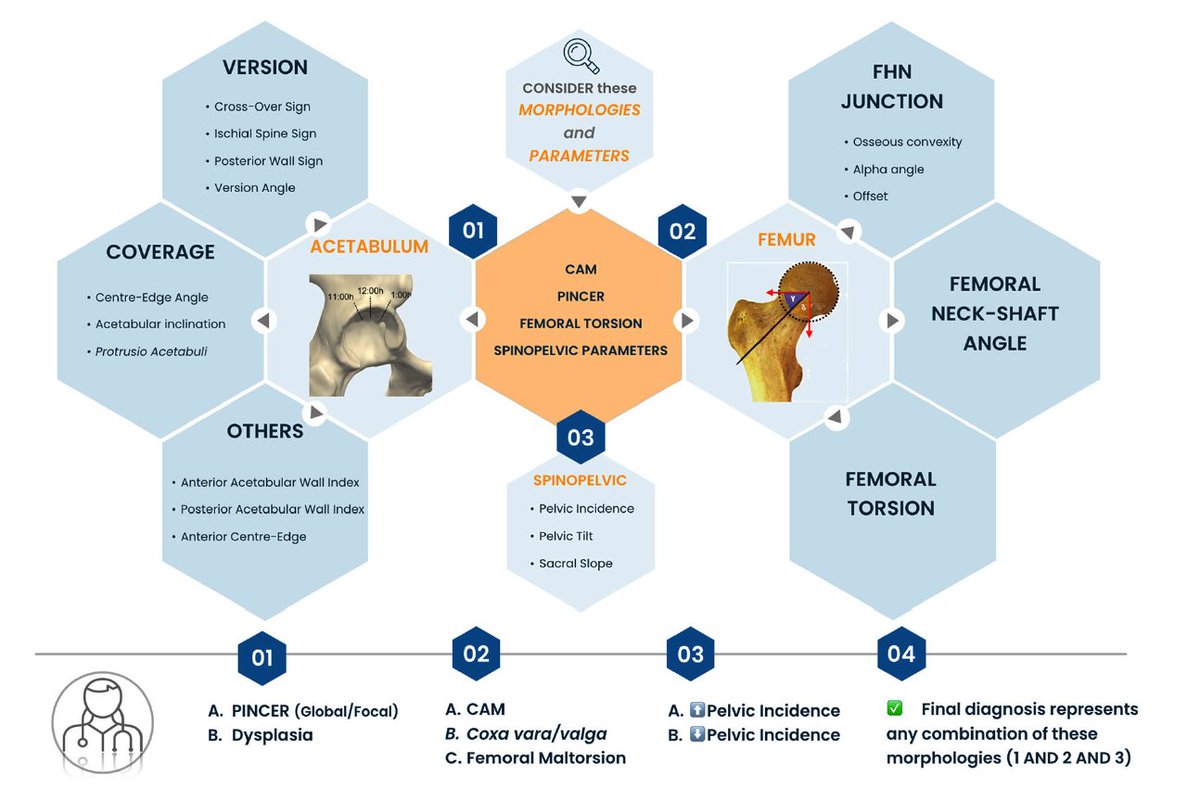

FAI week! Parts 2 & 3 of Lisbon "trilogy" on FAI imaging Control Hip Hype!

Part 2: https://pubmed.ncbi.nlm.nih.gov/33411052/

Part 3: https://pubmed.ncbi.nlm.nih.gov/33411053/